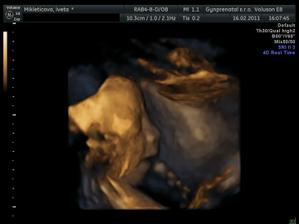

Čakáme miminko!